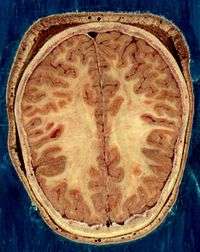

The living brain is very soft, having a gel-like consistency similar to soft tofu. Although referred to as grey matter, the live cortex is pinkish-beige in color and slightly off-white in the interior.

A gene present in the human genome but not in the chimpanzee (ArhGAP11B) seems to play a major role in corticalization and human encephalisation. The cerebral cortex is essentially a sheet of neural tissue, folded in a way that allows a large surface area to fit within the confines of the skull. When unfolded, each cerebral hemisphere has a total surface area of about 1.3 square feet (0.12 m2).[16] Each cortical ridge is called a gyrus, and each groove or fissure separating one gyrus from another is called a sulcus.

- ↑ From the National Library of Medicine's Visible Human Project. In this project, two human cadavers (from a man and a woman) were frozen and then sliced into thin sections, which were individually photographed and digitized. The slice here is taken from a small distance below the top of the brain, and shows the cerebral cortex (the convoluted cellular layer on the outside) and the underlying white matter, which consists of myelinated fiber tracts traveling to and from the cerebral cortex.